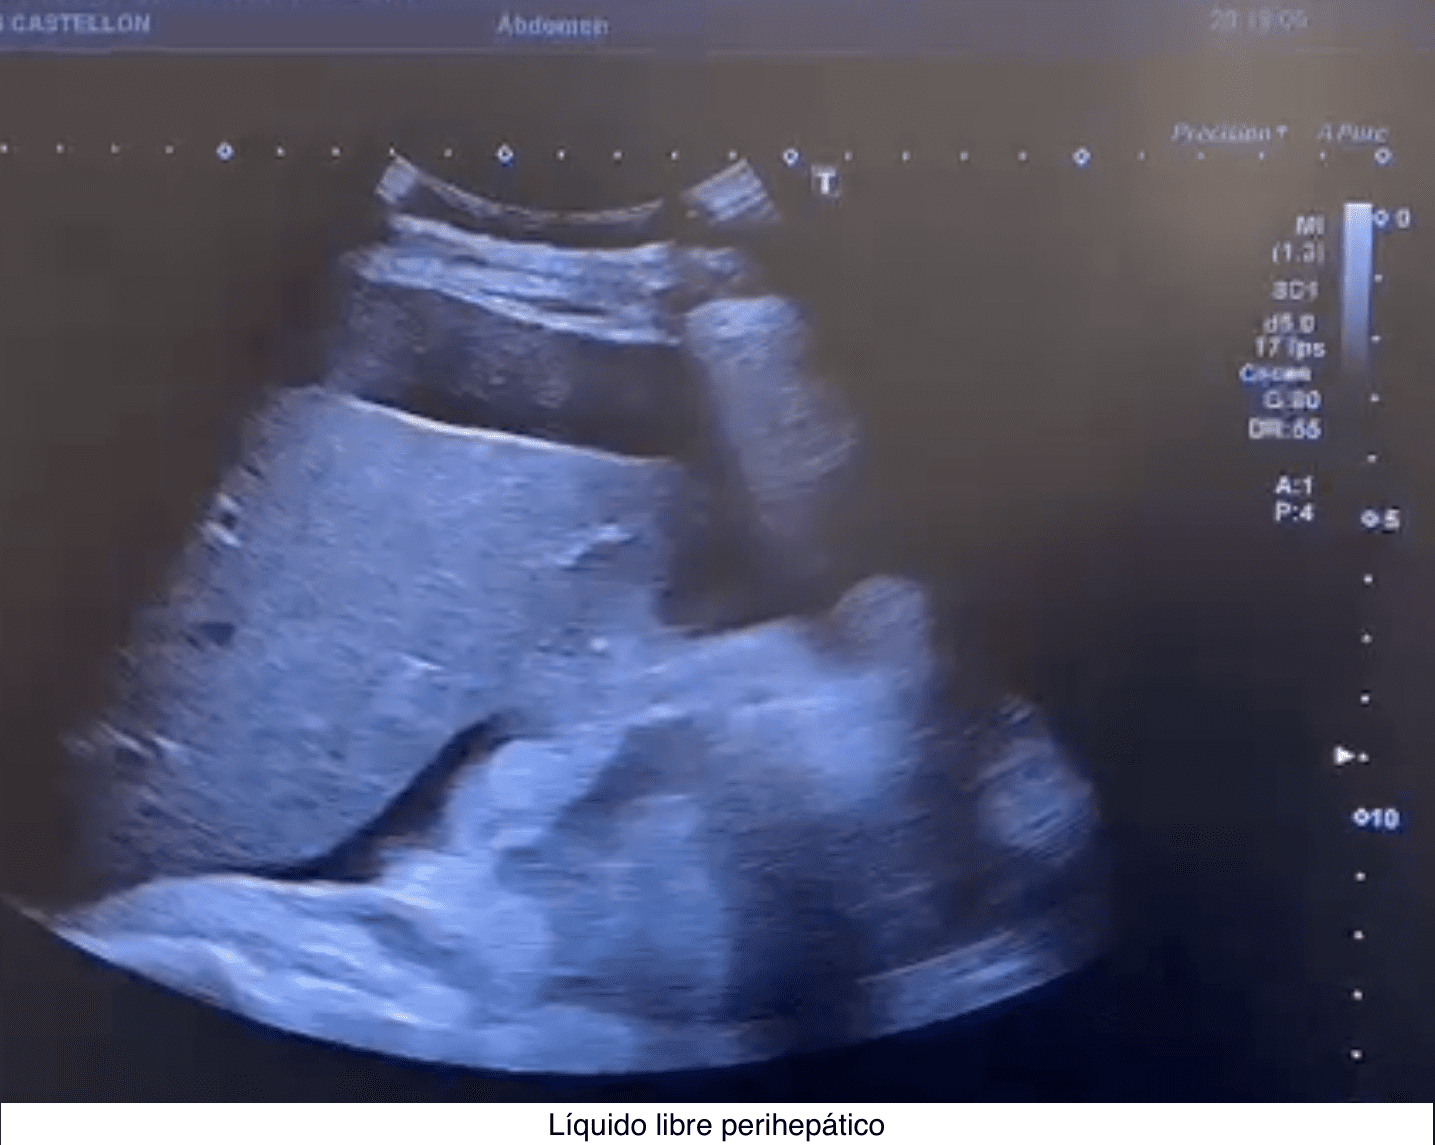

Se hace una ecografía abdominal a pie de cama, objetivando líquido ascítico junto líquido libre perihepático, periesplénico y pelvis inferior, sin otros hallazgos.